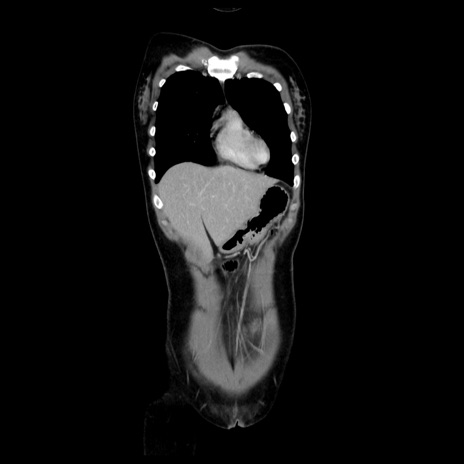

MRI(4日後)